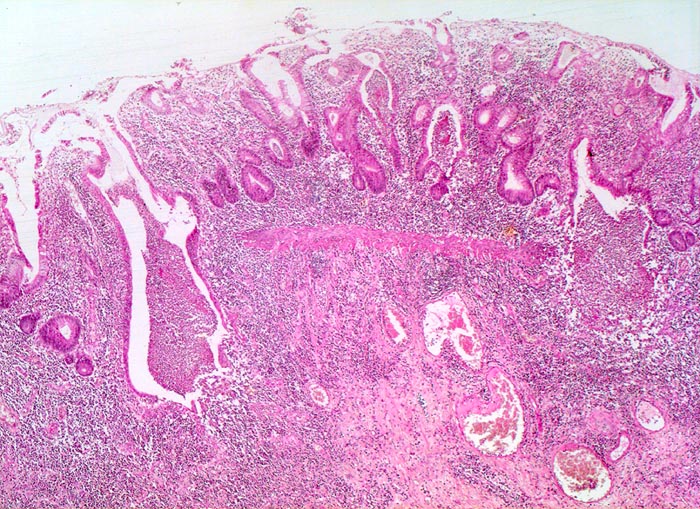

Die Colitis ulcerosa beginnt im Rektum (> 2758) und breitet sich kontinuierlich nach proximal aus. In 10% ist das gesamte Kolon (> 3364) befallen und es besteht zusätzlich eine back-wash-Ileitis im terminalen Ileum. Das Rektum ist bei unbehandelten Patienten praktisch immer befallen. Nach topischer Therapie kann das Rektum ausgespart sein und nach längerem Krankheistverlauf ist auch ein segmentaler Befall möglich. Bei fehlenden klinischen Angaben (Dauer der Erkrankung, Therapie) können diese atypischen Manifestationen diagnostische Schwierigkeiten verursachen. Makroskopisch finden sich häufig longitudinal ausgerichtete Ulzera mit Querverbindungen und Konfluenz. Residuelle Schleimhautinseln imponieren als Pseudopolypen. In der Remissionsphase ist die Schleimhaut glatt und blass, das Faltenrelief ist vergröbert und verstrichen und es finden sich häufig Granulationsgewebspolypen. Mikroskopisch findet sich je nach Entzündungsaktivität eine mehr oder weniger ausgeprägte diffuse Verdichtung des lymphoplasmazellulären Entzündungsinfiltrates mit Beimischung von Granulozyten in Form einer Kryptitis oder von Kryptenabszessen. Bei einer stark aktiven Entzündung finden sich zusätzlich Erosionen und Ulzera mit Ausdehnung der Entzündung über die Mukosa hinaus in die Submukosa oder in noch tiefere Schichten bei hochflorider Kolitis. Die Kryptenarchitektur ist gestört, die Anzahl der Krypten und der Becherzellen vermindert. In der Regeneratphase finden sich zahlenmässig reduzierte und verkürzte Krpyten mit normaler Anzahl Becherzellen. Meist bleibt eine leichte Verdichtung der Entzündungszellen in der Lamina propria bestehen.

Morphologische Merkmale:

• Abwechslungsweise oberflächliche Ulzera und pseudopolypöse Schleimhautvorwölbungen.

• Entzündungsinfiltrate in Mukosa und Submukosa.

• Unregelmässig geformte und verzweigte Krypten (Kryptenarchitekturstörung).

• Krpyten enden deutlich oberhalb der Lamina muscularis mucosae (Kryptenatrophie).

• Verminderte Schleimbildung und Becherzellverlust.

• Basal betonte Plasmozytose und Infiltrate neutrophiler Granulozyten.

• Ansammlungen neutrophiler Granulozyten in Kryptenlumina (=Kryptenabszesse) und Infiltrate von neutrophilen Granulozyten im Kryptenepithel (=Kryptitis).